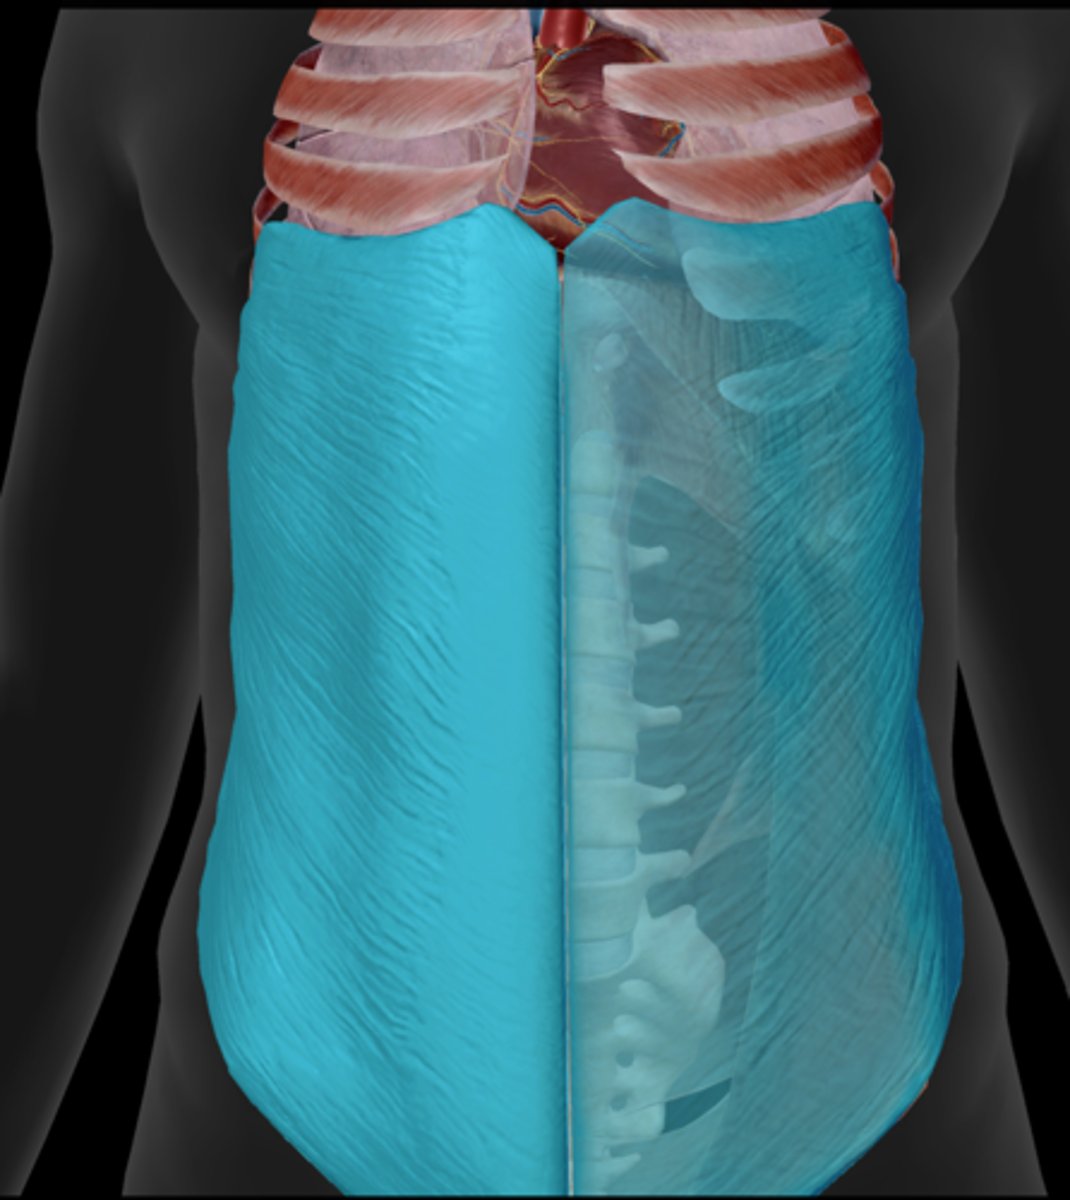

Diaphragm

Abdominals